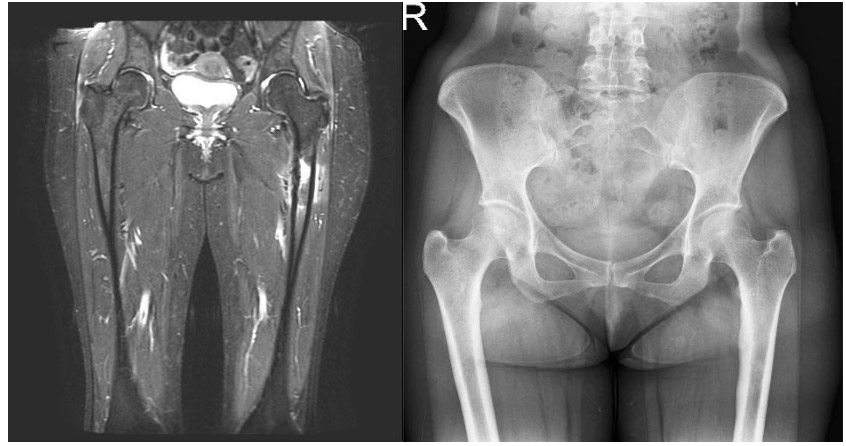

CASE 33: Risk of fracture and fracture development due to breast cancer metastasis to the upper end of the left thigh (femur).

- Hits: 22

First application: X-ray and MRI show a lytic lesion in the left proximal femur and surrounding edema.